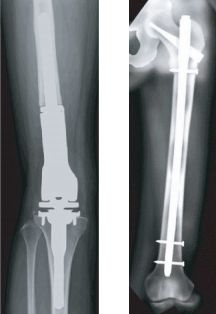

人工関節手術     骨折予防手術

転移性骨腫瘍

もともとの癌、たとえば肺癌や乳癌を担当した医師と共同で、抗癌剤、放射線治療、ホルモン治療、骨吸収抑制剤などを用いた治療を行います。骨折したり骨折の危険性がある場合には手術を行うこともあります。